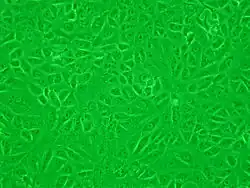

Linia komórkowa Vero

Linia komórkowa Vero (w esperanto: verda reno znaczy „zielona nerka”) – linia komórkowa pochodząca z tkanki nabłonkowej pobranej z nerki kotawca zielonosiwego[1][2][3][4].

Jest to ciągła, aneuploidalna linia komórkowa o komórkach podobnych do fibroblastów[3], którą można pasażować w nieskończoność w warunkach laboratoryjnych[5]. Umożliwia produkcję szczepionek przeciw chorobom wirusowym[6]. Wykorzystuje się ją w badaniach naukowych z mikrobiologii, biologii komórkowej i molekularnej[7].